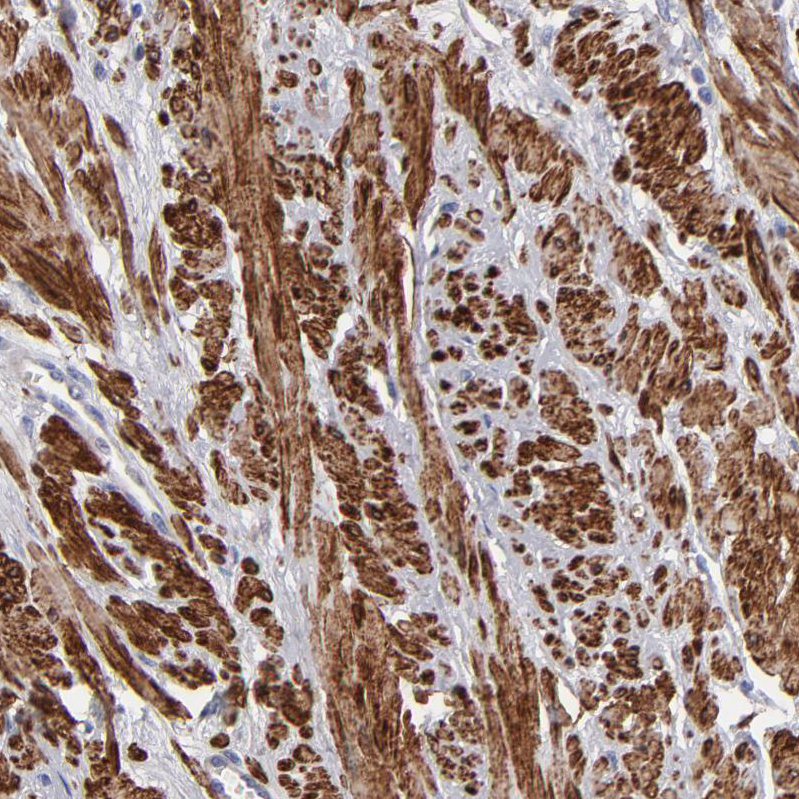

Immunohistochemistry analysis in human smooth muscle and liver tissues using Anti-SLMAP antibody. Corresponding SLMAP RNA-seq data are presented for the same tissues.